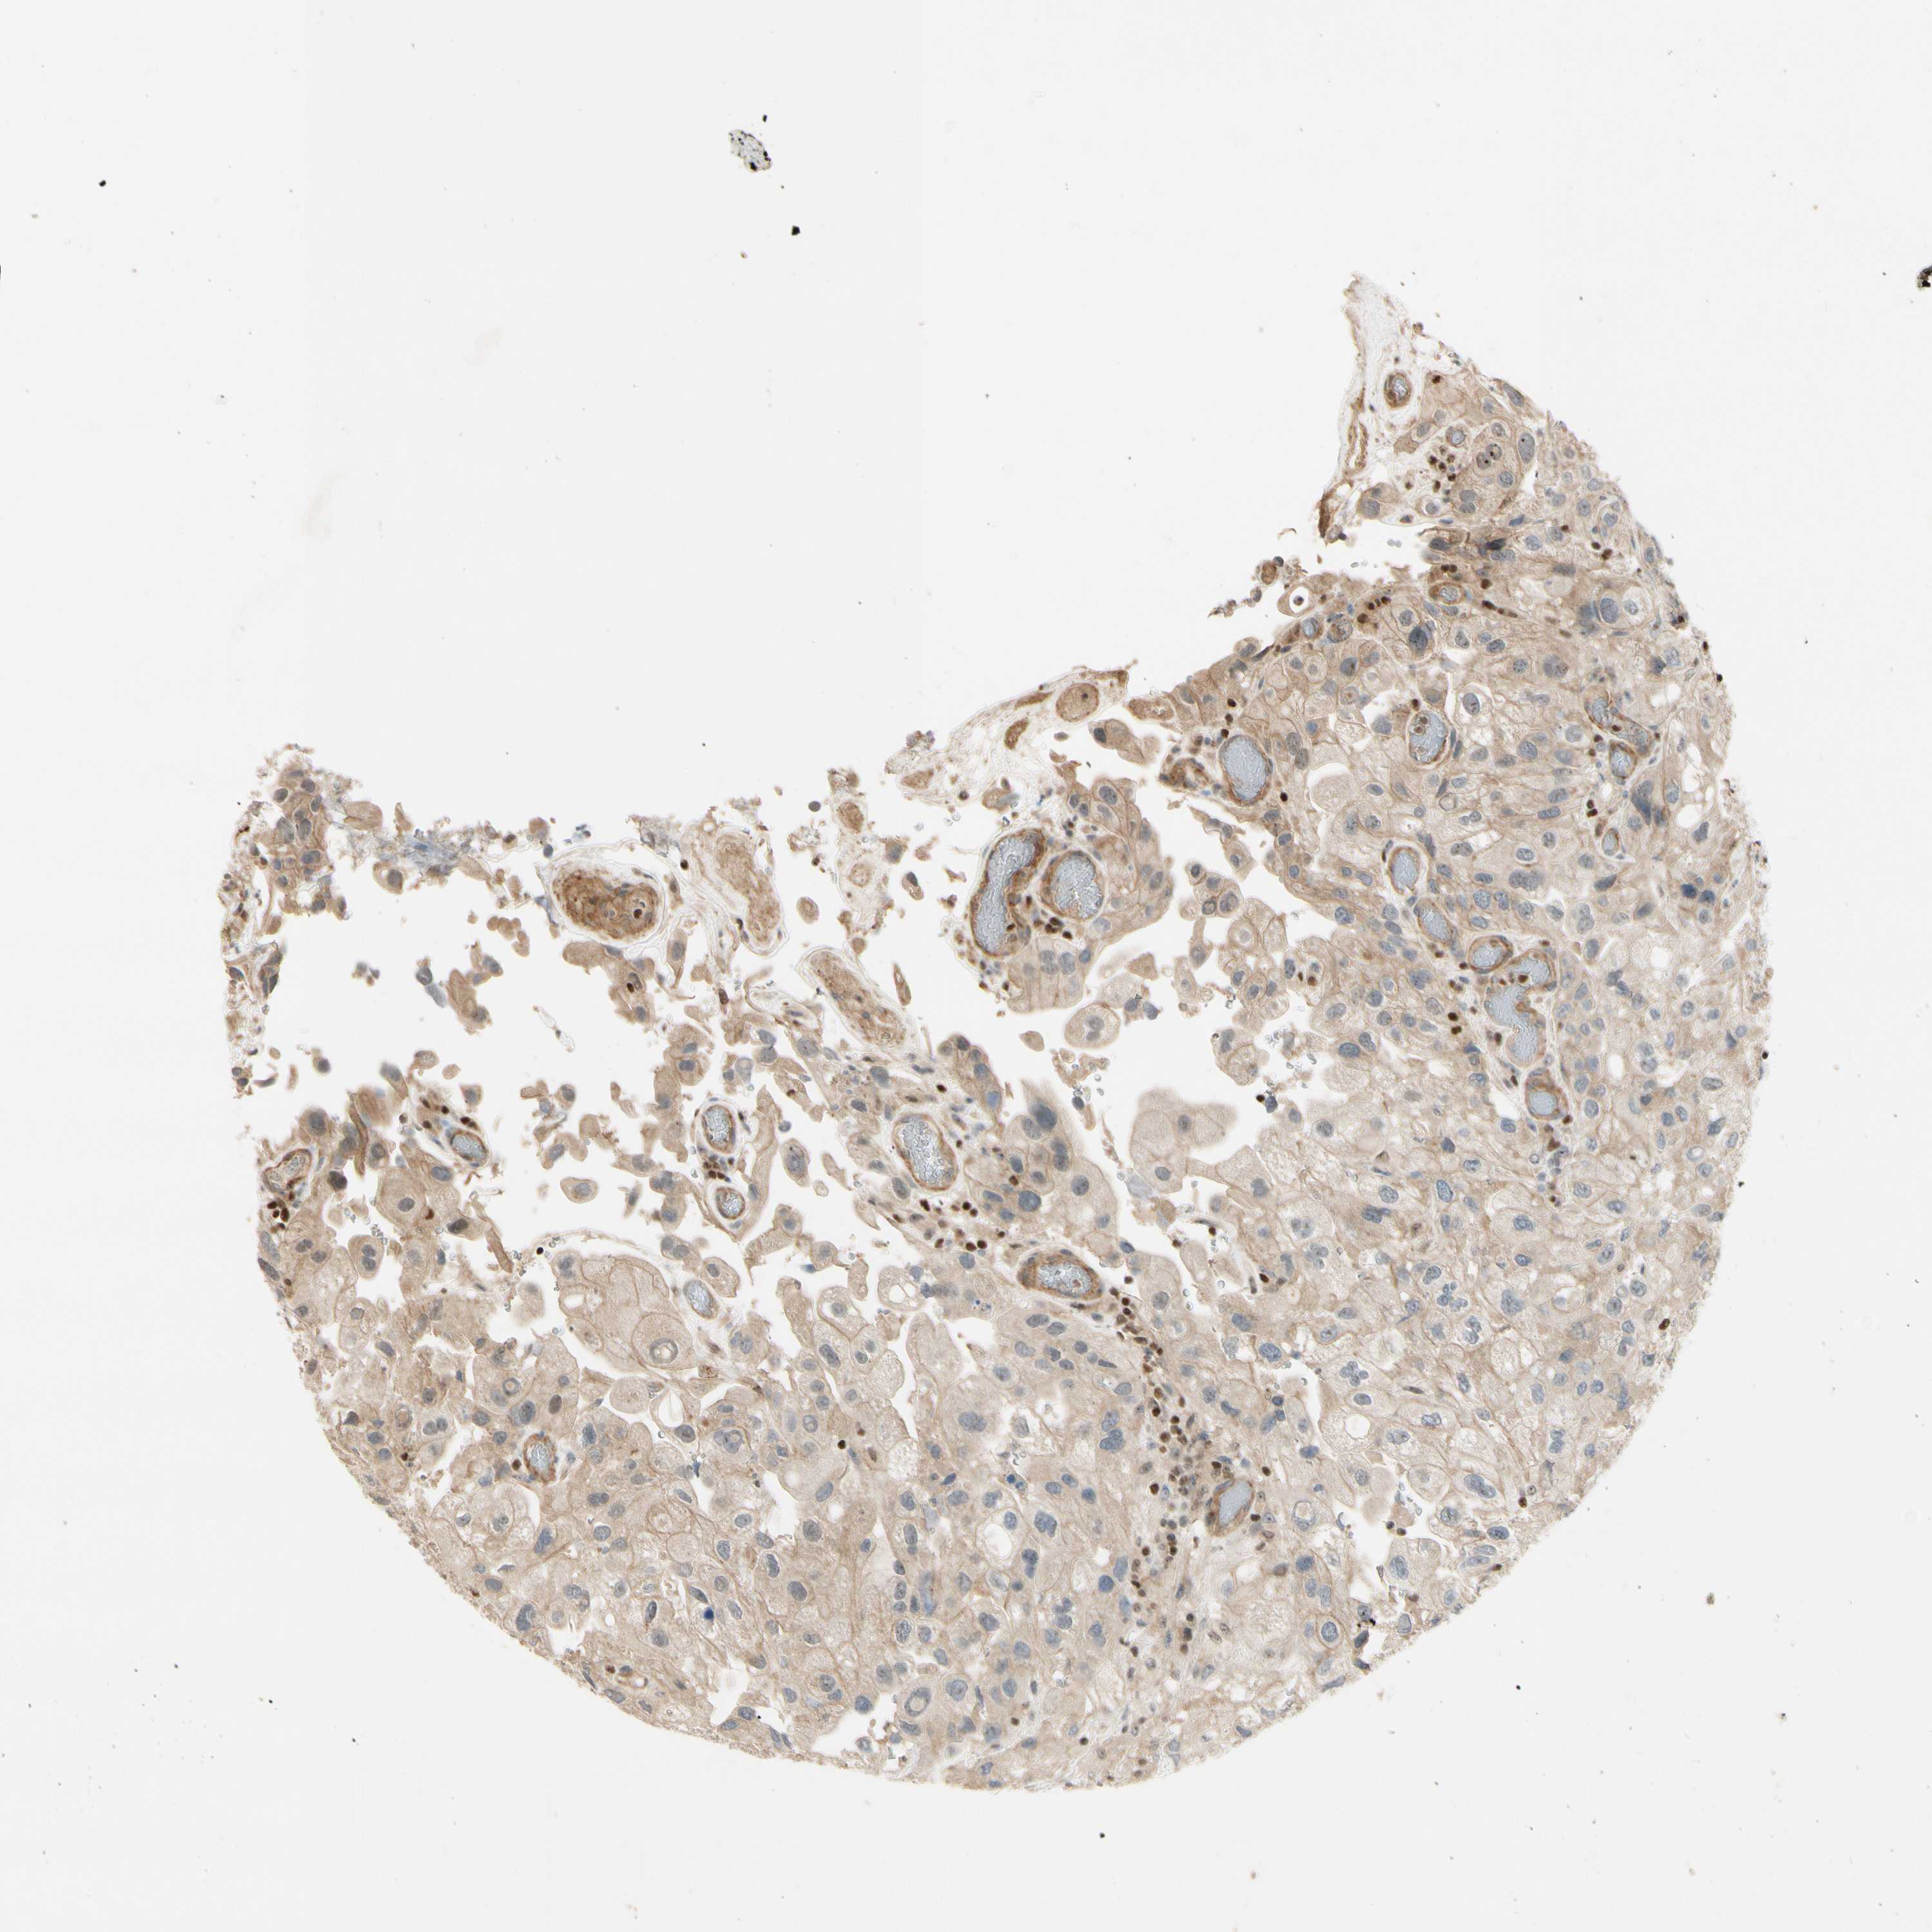

UROTHELIAL CANCER - Protein expressioni

A mouse-over function shows sample information and annotation data. Click on an image to view it in a full screen mode. Samples can be filtered based on level of antibody staining by selecting one or several of the following categories: high, medium, low and not detected. The assay and annotation is described here.

Note that samples used for immunohistochemistry by the Human Protein Atlas do not correspond to samples in the TCGA dataset.

Antibody stainingi

Antibody staining in the annotated cell types in the current human tissue is reported as not detected, low, medium, or high, based on conventional immunohistochemistry profiling in selected tissues. This score is based on the combination of the staining intensity and fraction of stained cells.

Each image is clickable and will lead to virtual microscopy that enables deeper exploration of all samples and also displays staining intensity scores, fraction scores and subcellular localization as well as patient and tissue information for each sample.

Antibody HPA050779

Antibody CAB009250

Urothelial carcinoma, High grade

Urothelial carcinoma, NOS

Urothelial carcinoma, Low grade